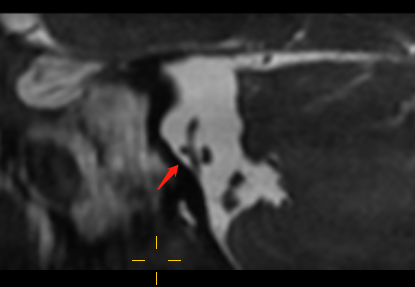

3DFIESTA 显示右侧小脑下前动脉穿行于面神经和前庭耳蜗神经间隙,并进入内耳道外口约 4 mm,神经与血管间隙消失,前庭耳蜗神经稍受压向外弯曲;左侧小脑下前动脉于内耳道外口穿行于面神经和前庭耳蜗神经间隙,局部接触、但无形态改变。

右小脑前下动脉迂曲延伸进入内听道神经与血管间隙消失,前庭耳蜗神经稍受压向外弯曲

前庭耳蜗神经延迟强化,右小脑前下动脉迂曲进入内听道